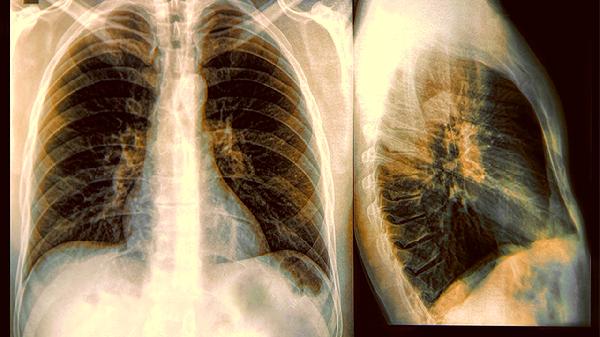

非特异性间质性肺炎能治好吗

非特异性间质性肺炎并不是不治之症,大多数患者在规范治疗下可以有效控制病情的发展。疾病的预后情况主要取决于病理类型、肺功能...